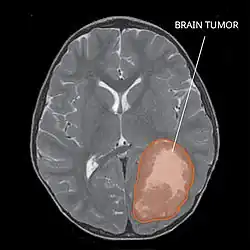

Magnetic resonance image of PNET

Most children that develop primitive neuroectodermal tumors are diagnosed early in life, usually at around 3–6.8 years of age.[2] Symptoms patients present at time of diagnosis include irritable mood, visual difficulties, lethargy, and ataxia.[2] The circumference of the patient's head might also become enlarged and they might be subject to seizures, especially if they have less than one year of life.[2]

Several analysis can be used to determine the presence of the disease. Physical examinations showing papilledema, visual field defects, cranial nerves palsy, dysphasia, and focal neurological deficits are evidences for possible tumor.[2] PNETs can also be spotted through computed tomography (CT) and magnetic resonance imaging (MRI).[2] In images produced by MRIs, an irregular augmentation among a solid mass will indicated the presence of tumor.[3] However, the results of MRIs are usually ambiguous in defining the presence for this specific tumor.[2] In CT scans, the presence of PNETs will be indicated by an elevated density and an increase in volume of the brain.[2] The CT scan can also show calcification,[3] which is present in 41-44% of PNET cases.[2] Since the tumor can be replicated in other parts of the nervous system through the cerebrospinal fluid (CSF), a CSF analysis can also be conducted.[2] A spinal MRI is a fourth type of analysis that is useful in investigating the level of tumor propagation to the spinal cord.[2]